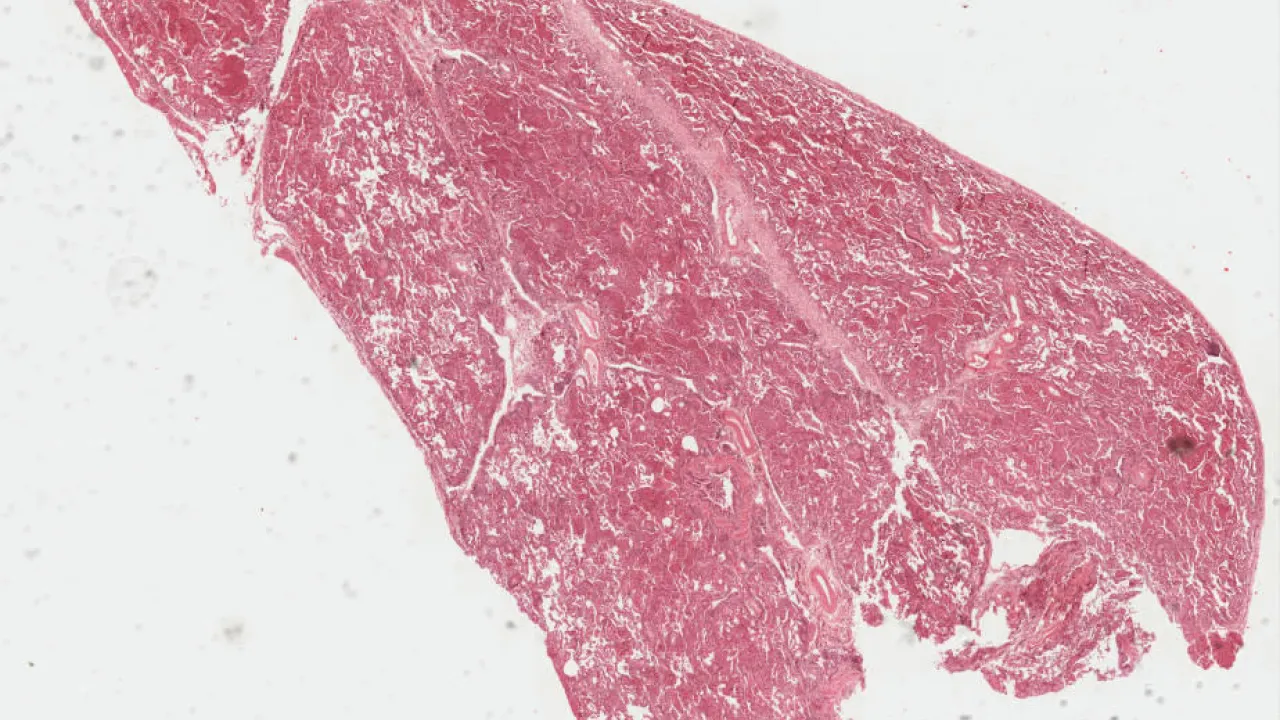

Lung

Pleura, Malignant mesothelioma, biphasic type

Lung, Malignant mesothelioma

Lung, Usual interstitial pneumonia

Lung, Cryptogenic organizing pneumonia